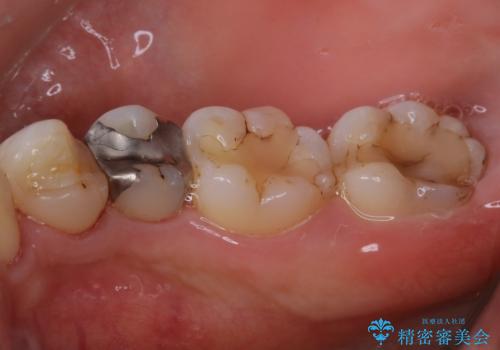

歯の表面に、茶色く色が残っている所がありますが、これは詰め物の変色の所と、虫歯になっている所です。以前に、CR(コンポジットレジン)による虫歯治療がされています。

CRは経年的劣化や、着色してしまうことがあります。PMTCでクリーニングを行うと、古いCRが目立つことがあるため、気になる際は詰め替えを行います。

茶色くなっている部分が、着色なのか、劣化なのか、虫歯によるものなのかは判別が難しいことがあります。そのため、定期的にPMTCを行うことで状態の確認が的確に行えます。

また、治療が開始される前などにも、全体的にクリーニングを行いご自身本来の歯の色、状態を精密に確認することが大切です。